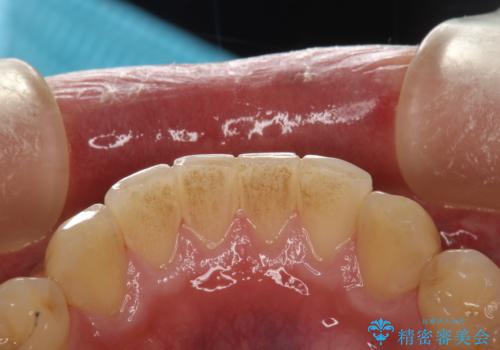

60分のPMTCで歯の黄ばみをきれいに除去

- 年末年始と忙しく、なかなか歯のケアがしっかりできなかった事と着色も気になるとのことで来院されました。PMTC60分コースを行いました。